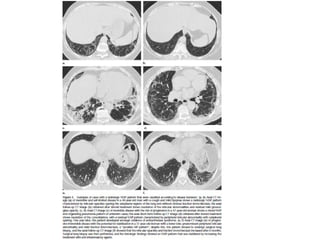

Aguda/subaguda COP • Ex BOOP •Asociada a : colágeno, infecciones, EII, radiación, toxicidad, transplante órganos Criptogénica: idiopática 55 h=m 4- 6 semanas con síntomas de gripe Buen pronóstico

COP CT • Consolidacionesparcheadas • Broncograma aéreo Signo halo inverso • Vidrio esmerilado periférico o peribroncovascular • Crazy paving • LI • Nódulos, cavitarse • Puede simular neumonía • Reticulación subpleural • Derrame pleural

DD COP • Infeccióny aspiración • Vasculitis, sarcoidosis, adenocarcinoma mucinoso, infoma • Si consolidación subpleural: neumonia crónica eosinofílica. Nódulos COP